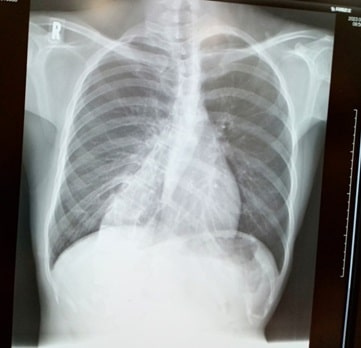

脊柱側弯症とは、背骨が左右に曲がったり、ねじれたりを伴うことがある状態です。

背骨がS字やC字のように曲がる。

軽度(レントゲン像で脊柱変形の程度を示すコブ(Cobb)角が25度未満の場合)の場合は経過観察のみ

中等度(コブ(Cobb)角が25度以上の場合)の場合は装具 (コルセット) 治療による矯正

重度(コブ(Cobb)角が80度以上の場合)の場合は背骨を矯正するための固定のための手術が必要な場合もあります。